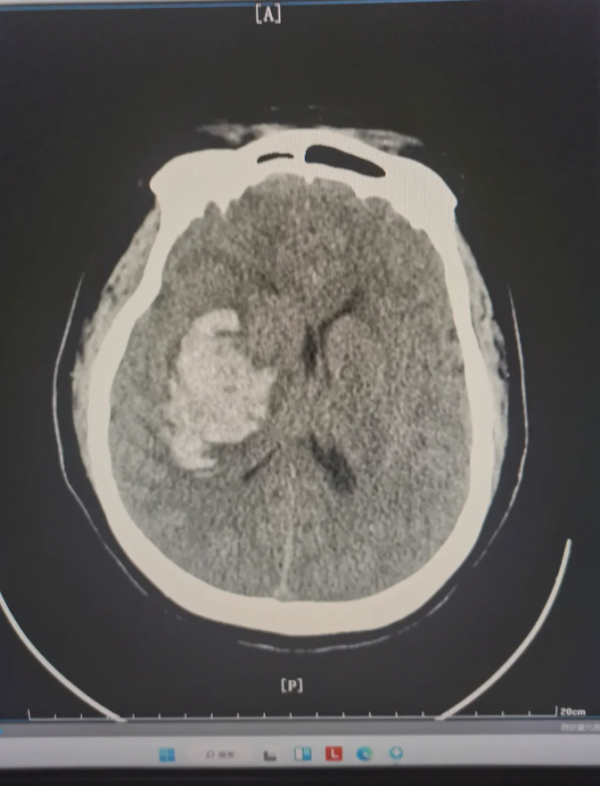

深夜,我院“120”接到急救电话,一名患者从床上跌落后出现左侧肢体无力、精神萎靡。急救人员抵达现场时,测得患者血压高达262/110mmHg,属极高危状态。紧急降压处理后,患者被快速转运至我院。急诊头颅CT检查显示:右侧基底节区急性脑出血,出血量达50ml,伴有明显脑水肿。患者随即被收入重症监护室(ICU)。

入院前